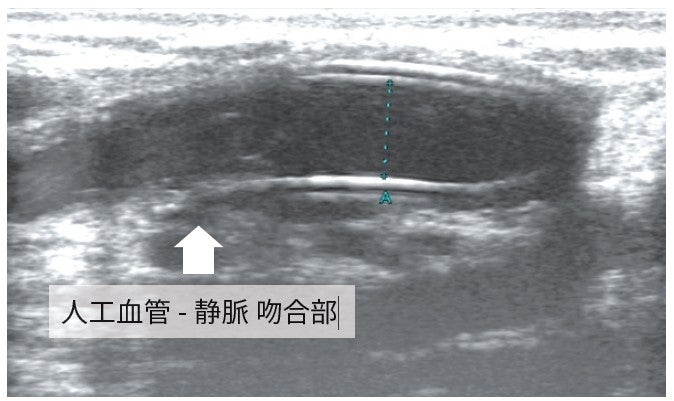

VIABAHN留置: まず、エコーを用いて人工血管と静脈の吻合部及び、病変部遠位端の皮膚にマーキングした。その距離は3.0 cmであった。デバイスの近位端を人工血管静脈吻合部の1 cm人工血管寄りとし、狭窄の遠位端の1 cm中枢まで留置するため、5 cm長を選択した。また、デバイス近位端の人工血管内径がエコーで5.0 mmと測定されたため(図3)、6 mm径を選択し、6 Frシースから0.018 インチガイドワイヤー (V-18™ Peripheral Guidewire**)で狭窄部を通過させた。皮膚にマーキングした位置をエコーで確認して、その部位にデバイスの遠位端を位置させた(図4)。エコーおよび透視で位置がずれないことを確認しながらVIABAHNを留置した。エコーにて近位端は人工血管内に1 cm ランディングできたことを確認した。VIABAHN 留置後、6 mmバルーンを用いて、nominal pressure で後拡張し、最後に血管造影を施行。狭窄部が良好に拡張したことを確認して、手技を終了とした(図5)。なお、VIABAHN 留置直後は、エコーで内腔を確認することはできなかった。